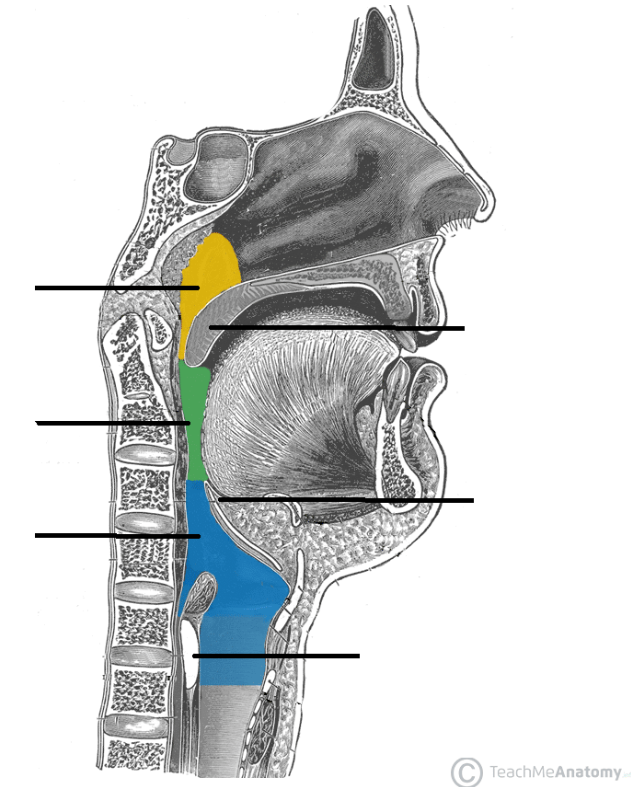

Nasopharynx

yellow highlight

Oropharynx

green highlight

Laryngopharynx

blue highlight